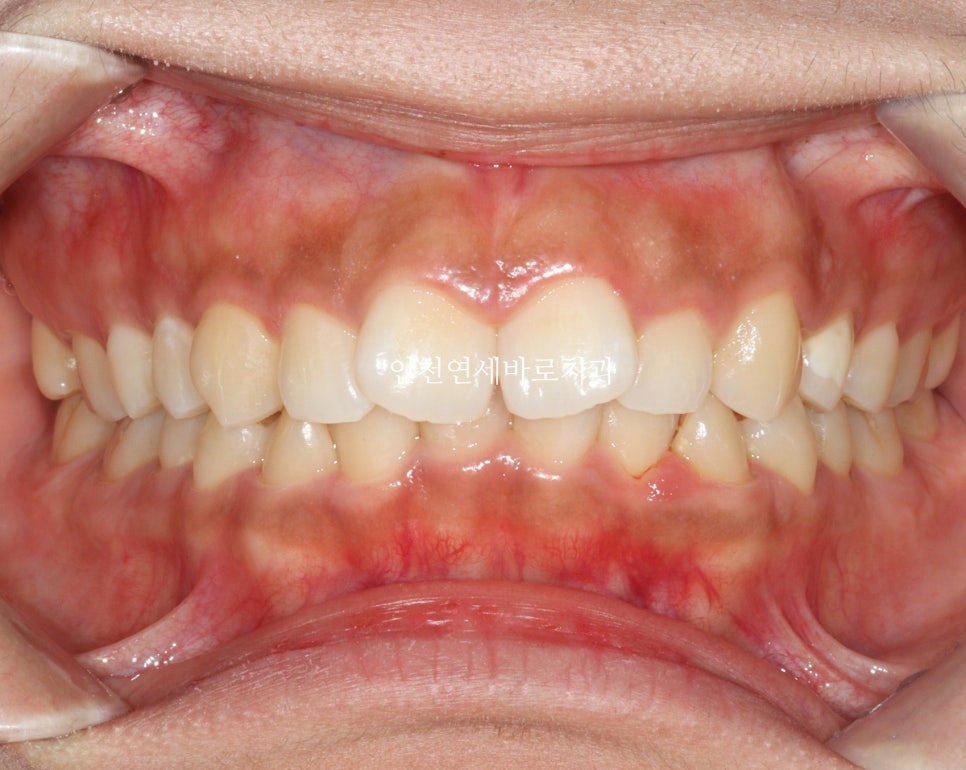

치료 전후 비교

전후 비교입니다

전 후 교합의 비교입니다.

안정적으로 교합이 형성되었습니다

교정 끝난 직후의 사진이라 아주 약간은 제 마음에 안드는 부분이 있지만